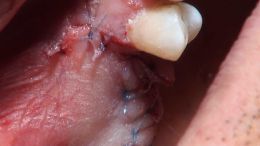

اصول مبانی GBR

+ اساتید گروه علمی بن تاژ پارس (زیرنظر پروفسور غلامی)

- جراحي توسط دکتر عميد از اساتید گروه علمی بن تاژ